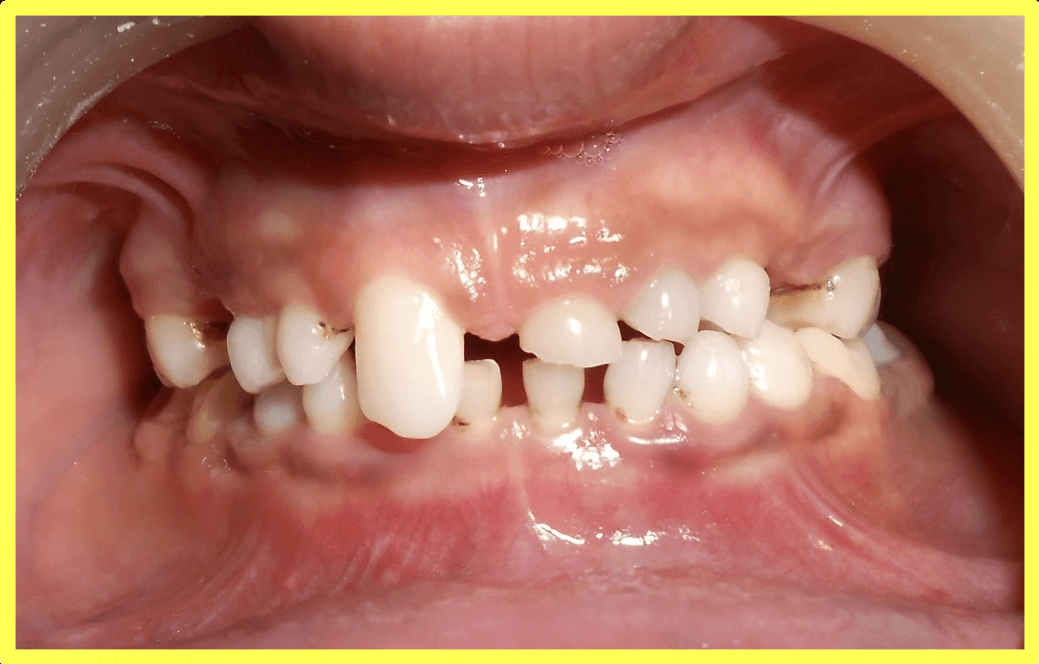

A 13-year-old male patient presented with oligodontia (congenitally missing permanent teeth) and retained deciduous (milk) teeth. Only two permanent lower molars were present. Treatment involved root canal therapy for all existing teeth followed by telescopic removable metallic PFM prosthesis for complete rehabilitation.

Upper and lower telescopic removable metallic PFM prosthesis was carefully fitted, adjusted, and delivered to restore complete dental function and aesthetics.